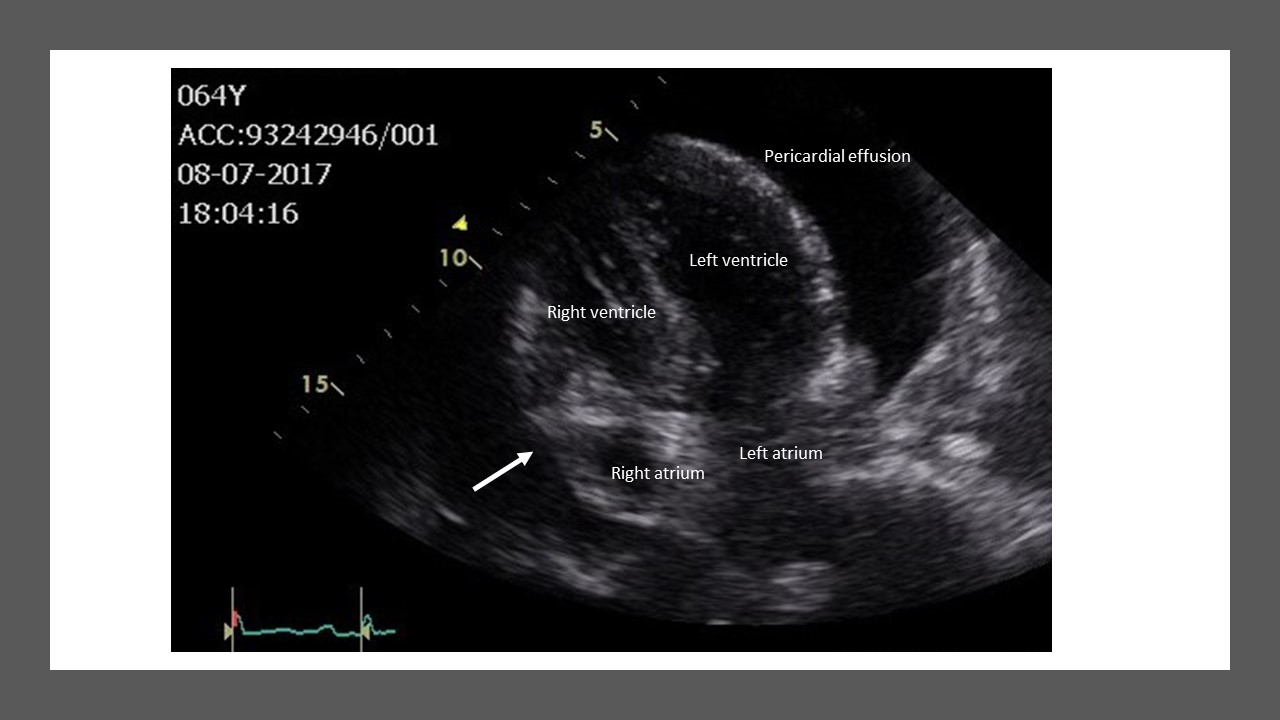

Tamponade Heart . Symptoms include a drop in blood. Can be rapidly fatal if not promptly drained through needle. It puts strain on the heart and stops it working effectively. cardiac tamponade is a medical emergency that takes place when abnormal amounts of fluid accumulate in the pericardial sac. This prevents the heart's ventricles from filling completely, which decreases the amount of blood the heart can pump to the body. cardiac tamponade occurs when the amount of fluid becomes too large and puts pressure on the heart. cardiac tamponade is a medical emergency; cardiac tamponade is a medical emergency in which fluid around your heart prevents it from pumping blood properly. cardiac tamponade results from pericardial fluid accumulating under pressure, impairing cardiac filling and. cardiac tamponade is when fluid collects around the heart muscle, for instance, due to trauma.